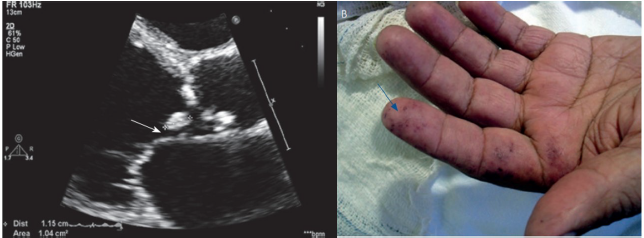

Paciente de 38 anos apresenta quadro de perda ponderal, febre de até 38,2° C, calafrios, queda do estado geral e lesões cutâneas não dolorosas em pés e mãos, com início há duas semanas. Refere ter valvopatia reumática e estar aguardando cirurgia na fila de hospital universitário de referência há mais de um ano. Ao exame: regular estado geral, FC 98 bpm, PA 112 x 70 mmHg, RCR 2T, bulhas normofonéticas com sopro sistólico 3+/6+ e diastólico 2+/6+ em foco aórtico, ausculta pulmonar sem alterações. Realizou a coleta de 3 pares de hemoculturas. Ecocardiograma do caso e lesões de pele reproduzidas abaixo.

Como vistas ao diagnóstico e ao tratamento, esse caso